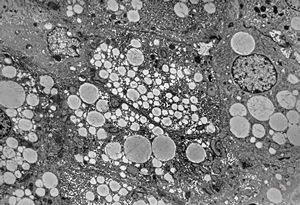

M,11y. | steatosis

M,14y. | steatosis

M,15y. | steatosis